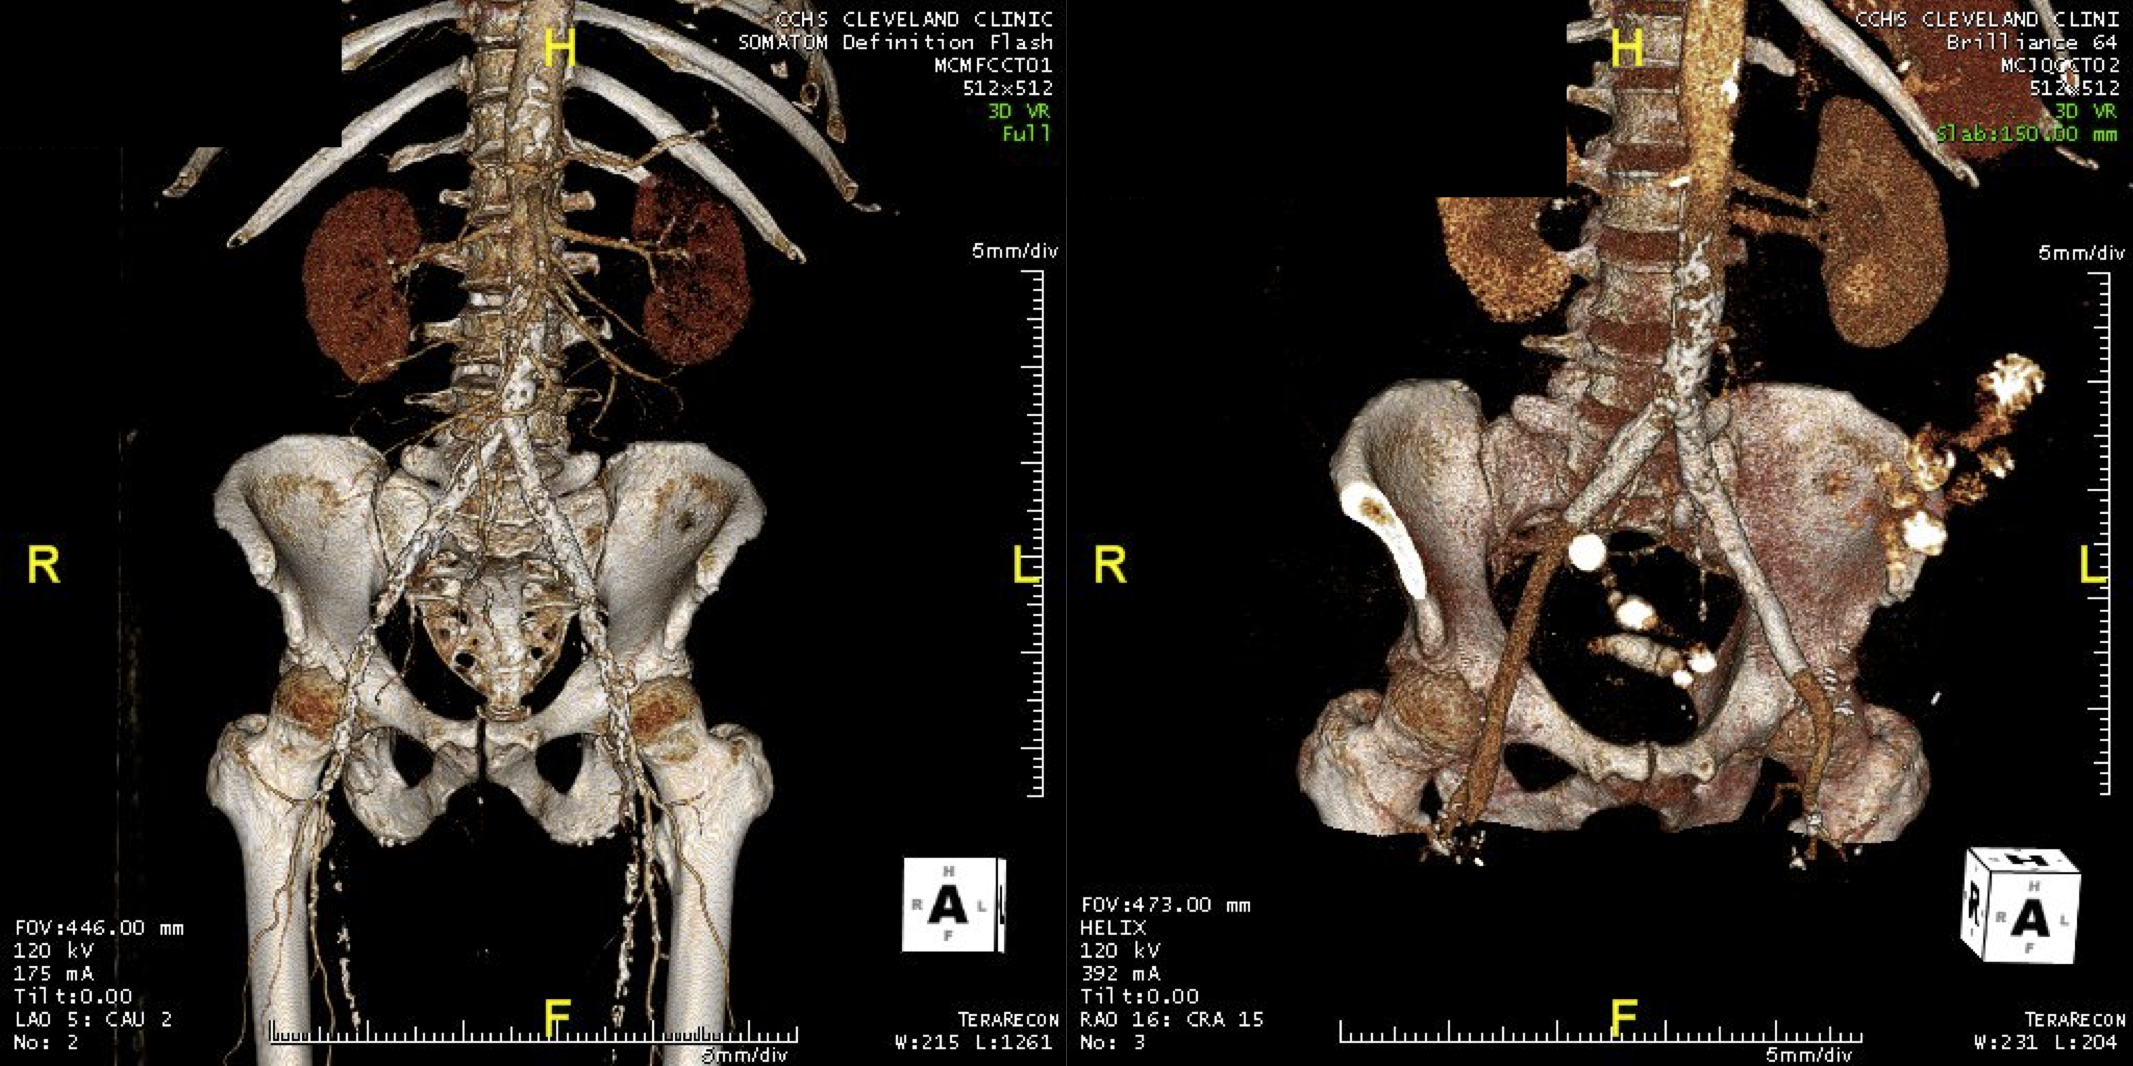

The EVAR was performed percutaneously. No endoleak was detected by completion arteriography (figure). He was soon discharged and was grateful. In followup, CT scan showed excellent coverage of the proximal and distal zones and absence of type III endoleaks. There was increased density to suggest a type II leak, but his inferior mesenteric artery was not the source of it. over a three year period, his aneurysm sac continued its 2-3mm of annual growth despite the presence of the the stent graft.

While CT failed to locate this endoleak, abdominal duplex ultrasound did showing flow from a small surface vessel (duplex below, figure at beginning of post). It was not the inferior mesenteric artery which can be treated endovascularly (link) or laparoscopically (link). CT scan suggested that it was one of those anterior branch vessels that one would encounter in exposing the aorta. Usually these were higher up as accessory phrenic arteries, but these fragile vessels, larger than vasovasorum, but smaller than named aortic branches, are seen feeding the tissues of the retroperitoneum.

Three years of followup showed growth of the AAA sac to 5.5cm, which ironically threshold for repair. Again, no type I or III endoleak could be seen. He reached his calculated repair date, and I discussed our options in detail.